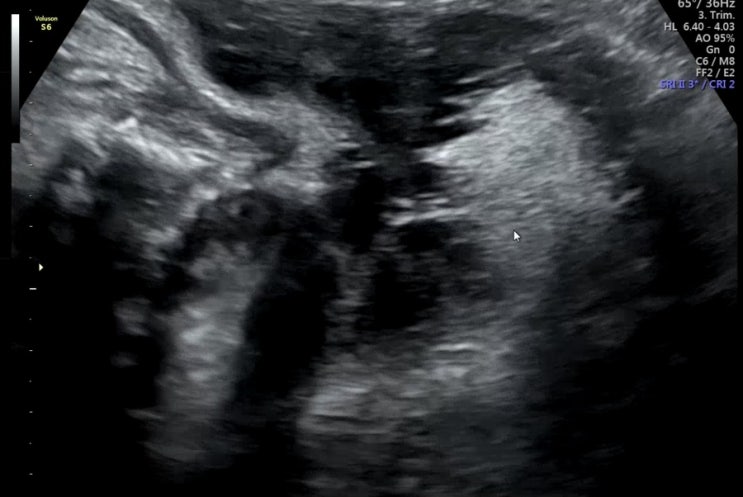

세가온산부인과 제왕절개 상세 후기

나중에 내가 보려고 쓰는 제왕 후기,,(긴글주의) 입원실 후기는 아래에 있움 ! https://m.blog.naver.com/b...